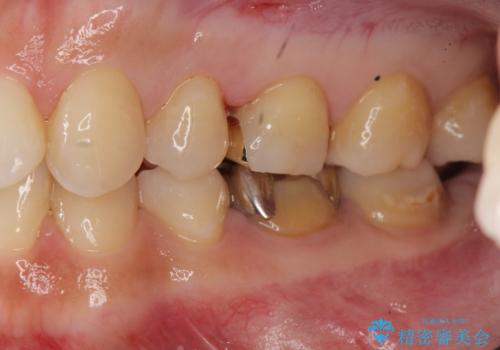

- 笑った時に目立つ、下の歯の銀歯をセラミックにしたいと来院されました。

症状・病変はなかったため根管治療は行わず、クラウンのやりかえのみの治療計画としました。

口腔内の金属を取り除くことで、健康的で明るい印象となりました。